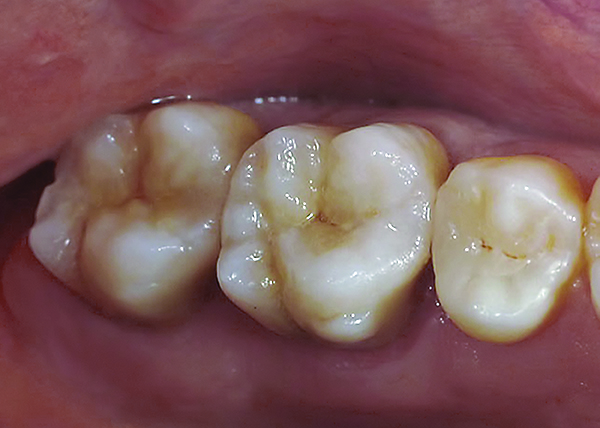

An example of this material subcategory is lithium disilicate (eg, IPS e.max®, Ivoclar Vivadent), a glass ceramic material composed of silica, lithium dioxide, alumina, potassium oxide, and phosphorous pentoxide. After the crystalline component has reached optimal growth through the manufacturing process, it is pulverized into powder and processed through a variety of different techniques.22 Lithium disilicate is indicated for the same clinical situations as other glass ceramics; however, when fabricated to a full-contour, monolithic restoration and seated with resin cement, it is also appropriate for higher stress situations, such as those requiring full crowns, even on molars (Figure 9 through Figure 11).

Figure 9 Preoperative preparation with composite block-out restoration, final cementation of Class IIb material, and final ceramic contour and stain by Steve Lee, CDT, MDC.

Figure 9

Figure 10 Preoperative preparation with composite block-out restoration, final cementation of Class IIb material, and final ceramic contour and stain by Steve Lee, CDT, MDC.

Figure 10

Figure 11 Preoperative preparation with composite block-out restoration, final cementation of Class IIb material, and final ceramic contour and stain by Steve Lee, CDT, MDC.

Figure 11